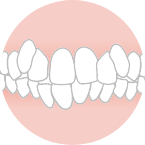

6人座っている状態

前歯が閉じない

(いわゆる受け口)